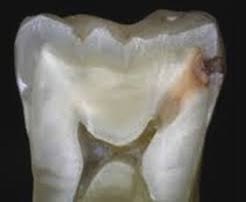

٣/التسوسات ما بين الأسنان:

هذه التسوسات عادة تحدث اذا لم تستخدم الخيط السني بإنتظام..وهذا النوع "الخفي" من التسوس يحتاج اكتشاف مبكر عن طريق أشعة من نوع خاص(الصورة ١)وتعمل هذه الأشعة عادة كل ٦ أشهر خلال الفحص الدوري.. الصورة ٢: مقطع عرضي لتسوس مايين الأسنان